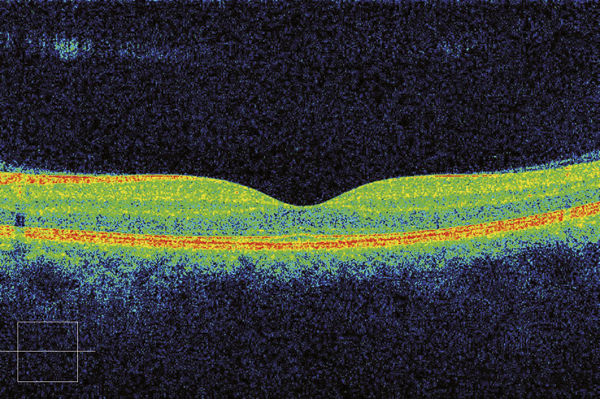

© Jean-François Korobelnik, La Revue du Praticien Tomographie en cohérence optique d'une rétine maculaire normale.